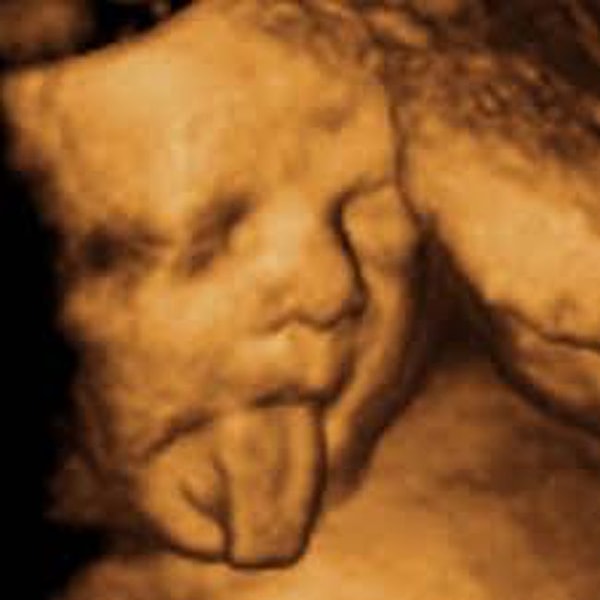

1. "Сестра показала снимок с УЗИ. Я предложила ей найти экзорциста".